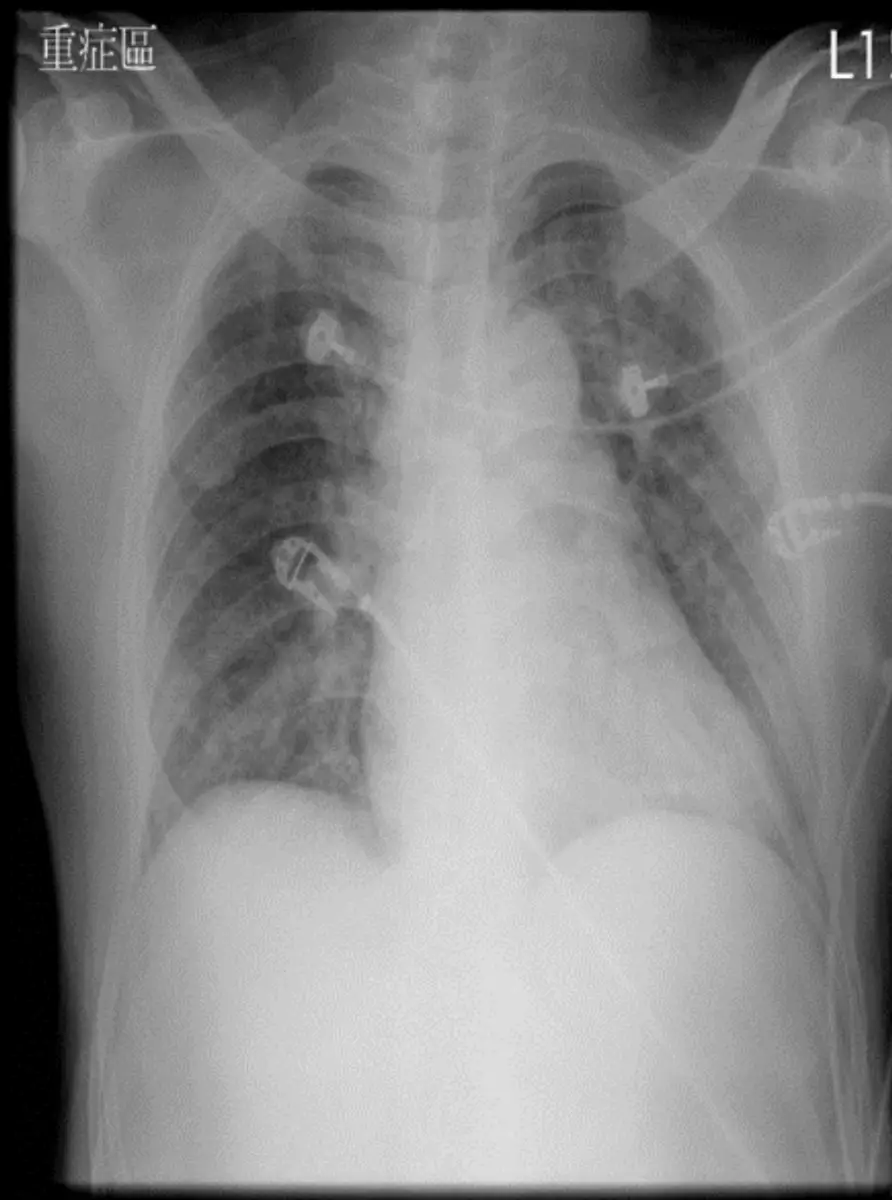

病人52歲男性,從下午逐漸感受胸部悶疼,走路時更有雙肩同步酸疼,又有冒汗及頭昏,在夜晚9:30更加 疼痛,乃急診求醫。無發燒、血壓、心跳、血氧及呼吸尚屬正常,心電圖如圖。 隨即靜脈注射 Unfractionated heparin,4000IU負荷劑量(Loading dose) ,維持每小時600IU劑量及口 服Aspirin325mg後,急送醫學中心處理。(EKG 1) 到院時E4V5M6; Vital signs: BP 118/79 mmHg, T/P/R 36.1/56/18,其他身體檢查尚屬正常。翌日清晨00:30再次心電圖(EKG 2)。胸部X光如圖:請問本病人最正 確的診斷是: 圖片描述 圖片描述 圖片描述